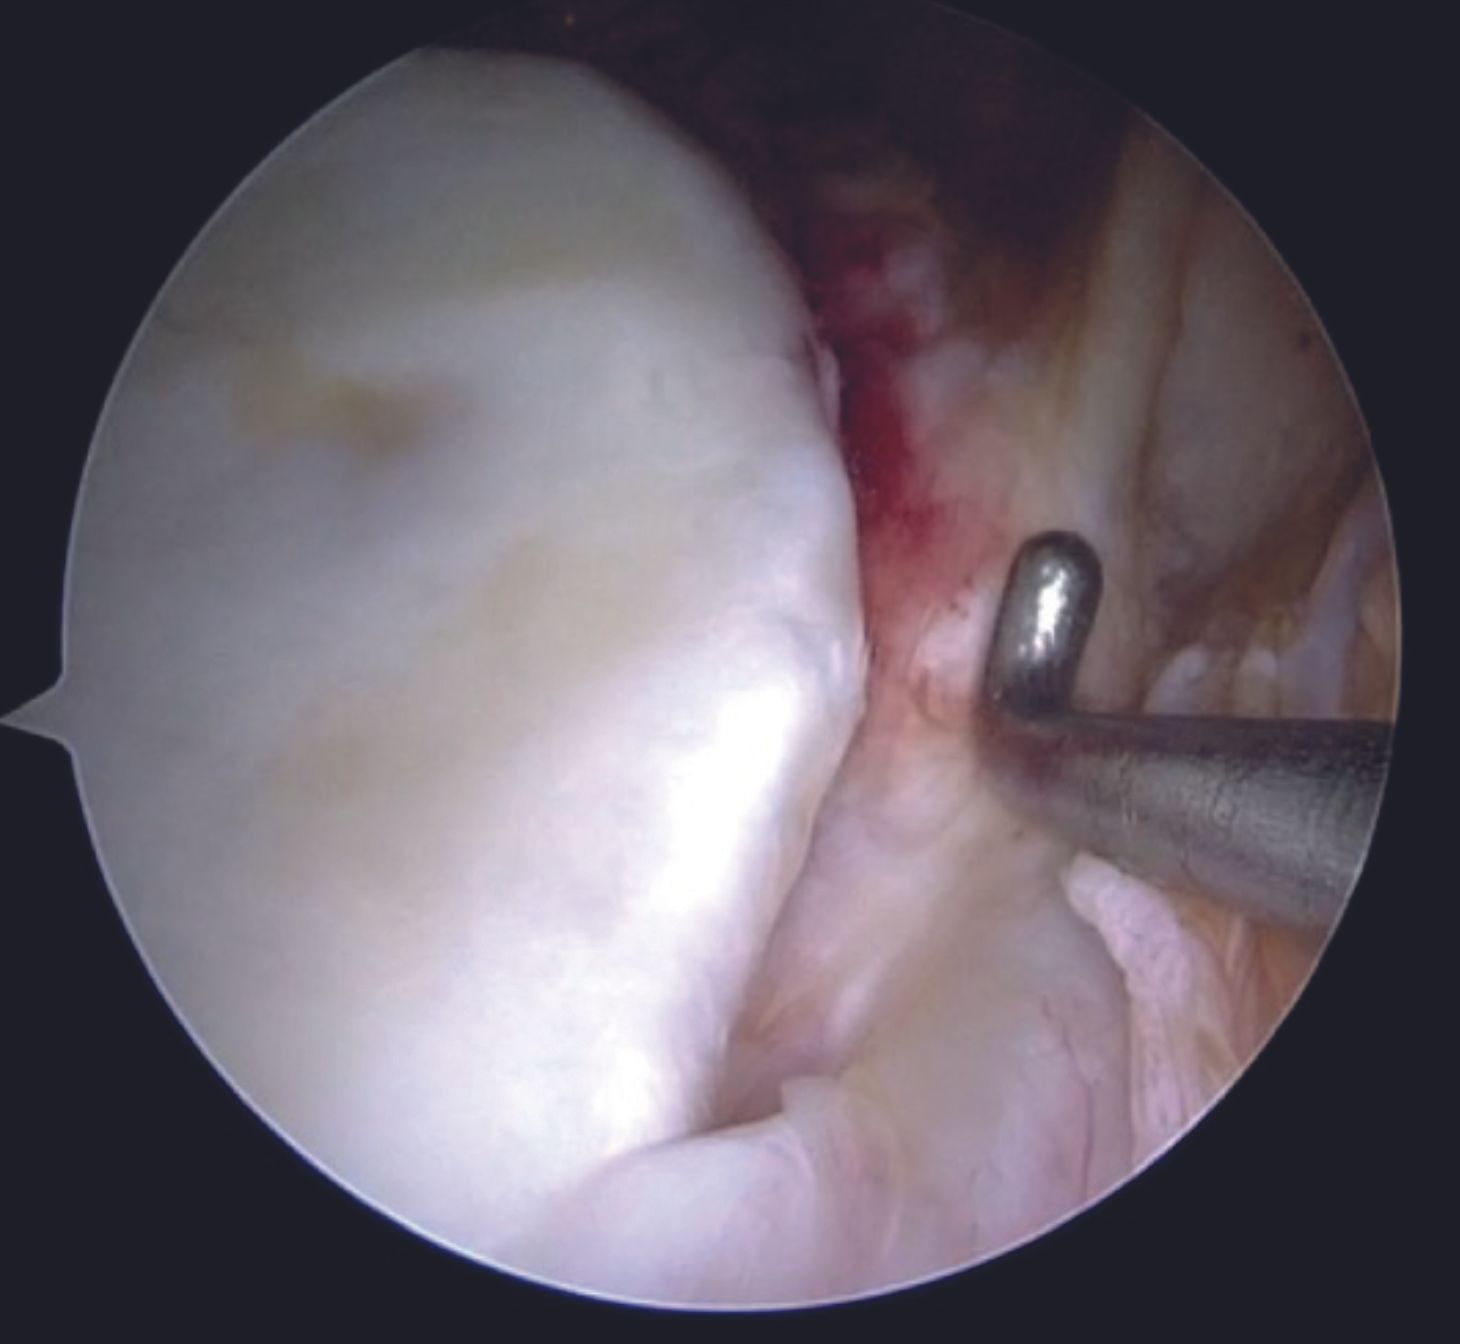

One of the tapes is then retrieved through the posterior portal with a tape retriever (Figure 11) and then shuttled through the labral tissue using a suture passer device (Figure 12,13).

A grasper can be utilized for holding the labral tissue in order to allow easy passage of the suture passer device. With both the tapes in the AI portal, a sliding Duncan loop knot is first tied (Figure 14), followed by at least three half hitches.

Care is taken to keep the knots away from the face of the glenoid by using the shuttled tape as a post and the other one as a throw. Before tying the sliding knot, utmost attention should be paid to provide adequate tension to the labral tissue by pulling the labrum superiorly with a grasper. Tapes are cut with an arthroscopic cutter around 4 to 5mm distal to the knot. One anchor each is placed at 4 and then at 3 O'clock position following a similar steps. After completion of the repair (Figure 15, 16), its integrity and stability is confirmed with a probe. After a thorough wash, closure is done with mattress sutures using 3-0 Ethilon.